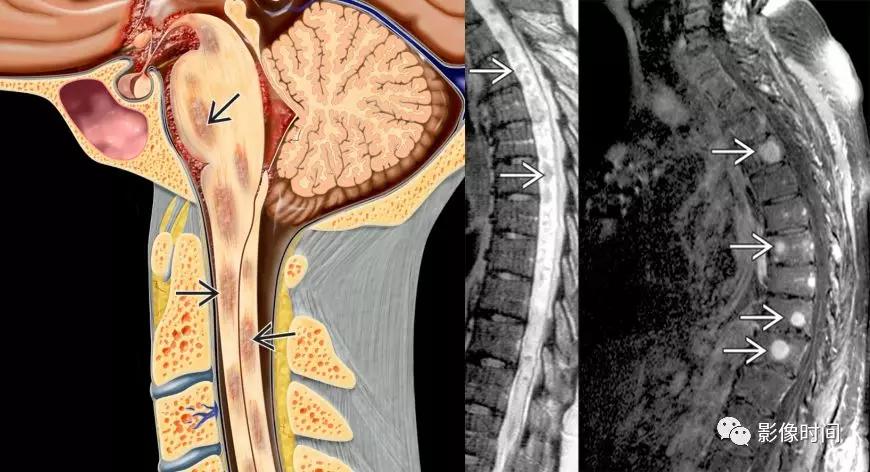

结节病(sarcoidosis):是一种系统性肉芽肿疾病,多器官存在非干酪性肉芽肿为主,累及中枢神经系统发病率为 14%–27% ,小于 10%CNS 结节病患者有脊髓病变。

MRI:

-

颈髓>胸髓

髓内长节段 T2WI 高信号(提示血管周围渗出)

脊髓表面多发结节状强化

颅内脑膜、脊膜多发强化(线样、结节状)

骨质异常强化

模式图显示脊髓内多发片状炎性渗出,T2WI 显示脊髓内长节段高信号,增强扫描椎体出现结节状强化出现多发结节状高信号

软脑膜出现线样强化,以小脑表面及基底池为主,额叶可见强化结节;脊膜出现结节状强化